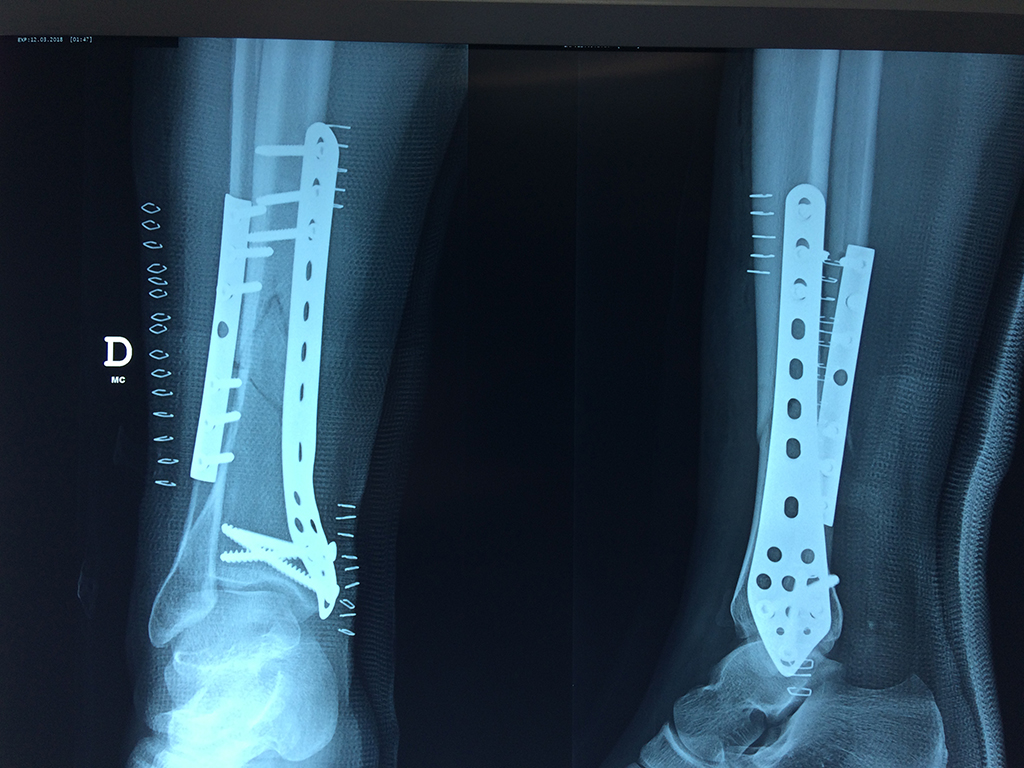

Cirugías de Húmero - Perone y Tibia

Aunque cada uno de estos huesos puede fracturarse por separado, normalmente la rotura es una lesión que se produce de forma conjunta

La mayor parte de las roturas implican a la parte proximal del hueso (parte del hueso próximo a la rodilla) o a la parte distal (parte del hueso cerca del tobillo).

Debido a la fina cobertura de piel que recubre la tibia y el peroné, las fracturas generalmente son abiertas, es decir, el hueso roto rasga la piel, atravesándola. Las fracturas de tibia y peroné generalmente se producen por un fuerte impacto o torsión.